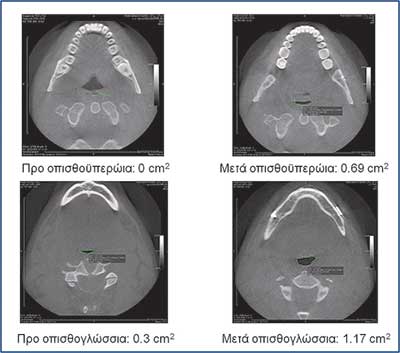

Οι εικόνες 4, 5 και 6 δείχνουν παραδείγµατα ασθενών που υποβλήθηκαν σε αµφιγναθική προώθηση. Στην εικόνα 4 πρόκειται για σύγκριση προεγχειρητικής µε 2 µήνες µετεγχειρητική πλάγια κεφαλοµετρική ακτινογραφία, όπου διακρίνεται η χοανοειδής διεύρυνση του φαρυγγικού αυλού στο οπισθοϋπερώιο και στο οπισθογλώσσιο τµήµα του. Ο συγκεκριµένος ασθενής βελτίωσε τον ∆ΑΥ από τα 100 επεισόδια / ώρα προεγχειρητικά στα 7 επεισόδια / ώρα µετεγχειρητικά, έτσι ώστε να µη χρειάζεται πλέον να κοιµάται µε τη ρινική µάσκα CPAP. Στην εικόνα 5α βλέπουµε µέση οβελιαία τοµή από υπολογιστική τοµογραφία του αεραγωγού ασθενούς µε προεγχειρητικό ∆ΑΥ 55 επεισόδια / ώρα και ελάχιστο καταγεγραµµένο κορεσµό αιµοσφαιρίνης 77%. ∆ιακρίνεται πλήρης οπισθοϋπερώια απόφραξη και πολύ σοβαρή οπισθογλώσσια στένωση. Στηνεικόνα 5β διακρίνεται ο σχεδιασµός της αµφιγναθικής προώθησης και της συµπληρωµατικής οριζόντιας γενειοτοµής στον ίδιο ασθενή. Στην εικόνα 5γπαρατίθεται η σύγκριση του εµβαδού διατοµής του φαρυγγικού αυλού αυτού του ασθενούς οπισθοϋπερώια και οπισθογλώσσια πριν και 1 έτος µετά την επέµβαση. Είναι εµφανέστατη η αύξηση των διαστάσεων του αεραγωγού. Οι εικόνες 6α και 6β αποτελούν πλάγιες και κατά µέτωπο τρισδιάστατες απεικονίσεις αεραγωγού ασθενούς πάσχοντος από βαρύτατο ΣΑΑΥ προ και µετά την αµφιγναθική προώθηση.

Εικόνα 5γ